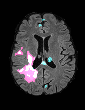

In recent years, data-driven machine learning (ML) methods have revolutionized the computer vision community by providing novel efficient solutions to many unsolved (medical) image analysis problems. However, due to the increasing privacy concerns and data fragmentation on many different sites, existing medical data are not fully utilized, thus limiting the potential of ML. Federated learning (FL) enables multiple parties to collaboratively train a ML model without exchanging local data. However, data heterogeneity (non-IID) among the distributed clients is yet a challenge. To this end, we propose a novel federated method, denoted Federated Disentanglement (FedDis), to disentangle the parameter space into shape and appearance, and only share the shape parameter with the clients. FedDis is based on the assumption that the anatomical structure in brain MRI images is similar across multiple institutions, and sharing the shape knowledge would be beneficial in anomaly detection. In this paper, we leverage healthy brain scans of 623 subjects from multiple sites with real data (OASIS, ADNI) in a privacy-preserving fashion to learn a model of normal anatomy, that allows to segment abnormal structures. We demonstrate a superior performance of FedDis on real pathological databases containing 109 subjects; two publicly available MS Lesions (MSLUB, MSISBI), and an in-house database with MS and Glioblastoma (MSI and GBI). FedDis achieved an average dice performance of 0.38, outperforming the state-of-the-art (SOTA) auto-encoder by 42% and the SOTA federated method by 11%. Further, we illustrate that FedDis learns a shape embedding that is orthogonal to the appearance and consistent under different intensity augmentations.